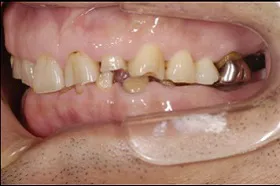

■治療前

| 主訴 | しっかりかみたい(咬合障害) |

| 治療方法 | 費用を抑える為、全てインプラントではなく、インプラントを土台とした入れ歯の治療 |

| 治療期間 | 約6か月 |

| 通院回数等 | 約20回 |

| 費用 | 約150万円 |

| リスク・副作用 | 術後の腫れ・痛み |